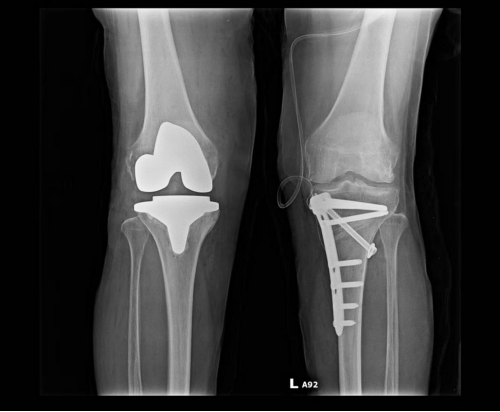

第三阶段治疗:如果患者膝关节病变集中在单侧,对侧关节里面软骨全层完整,膝关节内外侧副韧带及前后交叉韧带完好,则可行单髁置换术手术。 第四阶段治疗:膝关节内外侧关节软骨均损伤,比如类风湿性关节炎、强直性关节炎、膝关节的感染导致关节软骨破坏感染控制后等等,则需行全膝关节置换术。 (本图:左侧是截骨矫形内固定术后,右侧是全膝关节置换术后) 膝关节骨性关节炎阶梯治疗的有效路径及模式,可达到疾病有效治疗,保护有效劳动力,减少老年人因病致残生活不便引发的社会及家庭医疗负担。